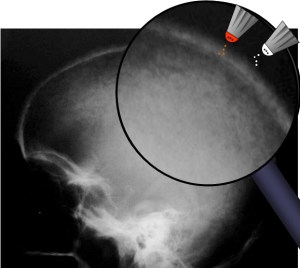

SIGNO DEL BRONCE BATIDO

El nombre de cráneo en bronce batido (o también cobre batido) hace referencia al aspecto de los huesos craneales con marcado aumento del patrón de circunvoluciones. La causa está en el aumento de la presión intracraneal que puede ser debido al cierre precoz de las suturas (craneosinostosis), hidrocefalia obstructiva, masas intracraneales o hipofosfatasia.

Afortunadamente, este signo es difícil de ver en la actualidad.

La imagen está cedida por el Dr. Leonard E Swischuk, quien ha otorgado el permiso para su publicación en esta web. Mi agradecimiento por su amabilidad.

Puedes consultar más en http://radiopaedia.org/articles/copper-beaten-skull

Este otro caso, reciente, me lo ha enviado mi compañera la Dra. Irene Bocanegra, del H. Materno-Infantil de Málaga. Muchas gracias por su aportación.